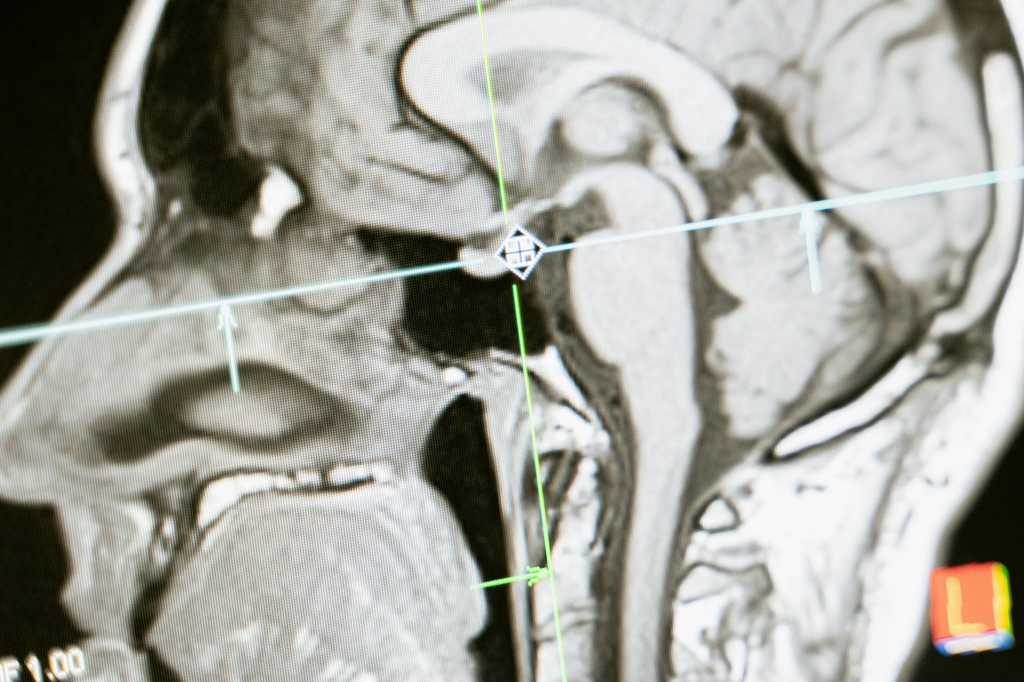

Mange danskere med senfølger efter hjernerystelse oplever i dag, at sundhedsvæsenet ikke kan tilbyde tilstrækkelig hjælp. En familie i Aarhus, Wikki Lund Hansen og Ali Eziddins 11-årige datter Isabella, har siden hun fik hjernerystelse for to år siden oplevet store begrænsninger i hverdagen. Isabella kan kun være i skole to til tre dage om ugen og i kortere perioder ad gangen, mens forsøg på at få støtte via Aarhus Kommunes hjernerystelseskoordinator og Hammel Neurocenter blev afvist.

Historien er ikke unik. En analyse fra Sundhedsstyrelsen viser, at behandlingen af hjernerystelse ofte kommer for sent og er utilstrækkelig. Ifølge eksperter som Frank Humle, direktør ved Center for Hjerneskade, og forskningsleder Hana Malá Rytter ved Dansk Center for Hjernerystelse, mangler der i dag tilbud til børn og unge, og behandling bør tilpasses den enkelte patients behov.